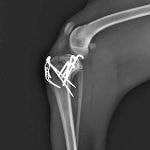

症例3:キルシュナーワイヤーのピンニングによる整復

ペルシャ猫 11ヶ月齢 雄

他院にて左大腿骨遠位の成長板骨折(salter-harrisⅠ型)が認められており、治療相談を目的として来院。当院にて、キルシュナーワイヤーを用いたピンニングにより骨折部位の整復を行いました。術後の経過は良好で、現在も経過観察中です。

術前レントゲン

術後レントゲン

Arthrex社のターゲティングデバイスを用いてピンニングの位置を調整することで、確実な固定を行っています。当院ではこの手術器具以外にも、人の手術にも使用される様々な器具を導入し、手術精度を高め、また医療メーカーと新しい器具の開発、試作にも取り組んでおります。